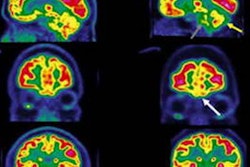

Compared with C-11 K-2 PET imaging in 80 healthy controls, a voxel-wise analysis indicated a statistically significant increase in radiotracer uptake across the brain overall as well as in specific regions of patients with long COVID, indicating increased AMPAR density, the researchers reported.

(A) Elevations in C-11 K-2 SUVR-WM in patients with long COVID memory impairment (Cog-LC) (n = 30) compared to healthy controls (HCs) (n = 80) (p < 0.05, T > 1.66, one-tailed, false discovery rate correction). (B) Multiple comparisons across Hammers’ VOIs between HCs (n = 80) and Cog-LC (n = 30). Bold line and dashed line of each plot represents mean and quartiles, respectively. *p < 0.05, **p < 0.01, ***p < 0.001 (Bonferroni multiple comparison test after two-way ANOVA analysis). (C) Brain regions showing a negative correlation between 11-C K-2 SUVR-WM and picture-naming scores of the RBANS in Cog-LC (n = 30) (p < 0.05, T > 1.71, one-tailed, false discovery rate correction). (D) Overlapping brain regions between the clusters in A and C. (E) Brain regions showing a negative correlation between 11-C K-2 SUVR-WM and figure recall scores of the RBANS in Cog-LC (n = 30) (p < 0.05, T > 1.71, one-tailed, false discovery rate correction). (F) Overlapping brain regions between the clusters in A and E. Abbreviations: A, anterior; P, posterior; R, right; L, left; FDRc, false discovery rate correction. Courtesy of Brain Communications

In addition, brain regions where C-11 K-2 tracer was significantly increased were negatively correlated with long-COVID patients’ picture naming and figure recall scores, which are RBANS subcategories, according to the results.